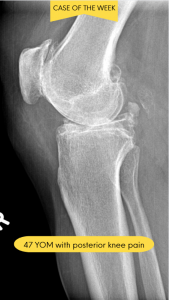

A 47-year-old male presents with chronic posterior knee pain that has progressively worsened over the past 18 months. The patient reports a dull, aching discomfort that intensifies with prolonged standing, stair climbing, and physical activity. He describes occasional episodes of sharp pain accompanied by a sensation of “catching” or “locking” in the knee joint. The patient notes morning stiffness lasting approximately 30 minutes and intermittent swelling around the posterior aspect of the knee. His medical history includes recreational basketball playing in his youth and a remote history of a knee sprain approximately 20 years ago. Conservative management with over-the-counter anti-inflammatory medications has provided minimal relief. Physical examination reveals moderate effusion, reduced range of motion, and crepitus with knee flexion and extension.

Fig. 1 Lateral view of the knee.

Fig. 2 Lateral view of the knee showing degenerative joint disease (DJD) and multiple osteochondral loose bodies in the posterior joint compartment.

Diagnosis: Osteochondromatosis Secondary to Degenerative Joint Disease

Based on advanced imaging studies and clinical correlation, the patient was diagnosed with osteochondromatosis secondary to degenerative joint disease (DJD). The radiology report revealed multiple intra-articular loose bodies within the posterior compartment of the knee joint, consistent with osteochondral fragmentation. Radiographic findings demonstrated moderate joint space narrowing, marginal osteophyte formation, and subchondral sclerosis, all characteristic features of underlying degenerative arthropathy. The presence of numerous calcified or ossified loose bodies confirmed the diagnosis of secondary osteochondromatosis resulting from progressive joint degeneration.